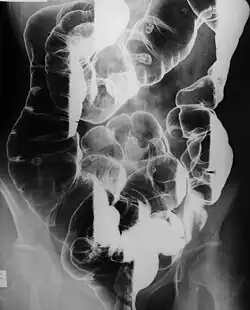

Die Krankheit manifestiert sich durch multiple gutartige Polypen im Magen-Darm-Trakt, wobei es sich dabei um Hamartome handelt. Histologisch zeigen sich dabei verzweigte glatte Muskelzellen mit eingelagertem Drüsengewebe. Oft finden sich mehrere hundert solcher Hamartome, die bei 88 % der Patienten nachweisbar sind. Sie sind in der Regel 1–5 mm groß, können aber auch bedeutend größer werden. Bei 64 % der Patienten sind sie im Dünndarm nachweisbar, in 64 % auch im Dickdarm (Colon), in 49 % im Magen und in 32 % im Enddarm (Rektum). Selten wurden die hamartomatösen Polypen auch im Nierenbecken, in der Blase, in den Lungen und in den Nasenlöchern beschrieben.[1]

Die Polypen werden typischerweise zwischen dem 10.–30. Lebensjahr klinisch manifest. Bei 43 % der Patienten manifestieren sie sich durch eine Obstruktion des Darmlumens bis zum Darmverschluss (Ileus), in 23 % durch abdominelle (kolikartigen) Schmerzen, und in etwa 14 % durch rektalen Blutabgang oder blutigen Stuhl. Selten (7 %) kommt es zu einer analen Extrusion eines Polypen. Häufig kommt es auch zu einer Einstülpung (Invagination) des Darms, meist (95 %) des Dünndarms. Durch chronische Blutungen kann sich eine sekundäre Anämie entwickeln.